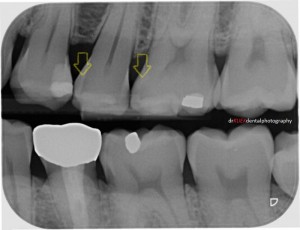

Dark shadows can be detected, though challenging to the untrained eye. Decayed teeth shown (Yellow arrows) on radiograph.

Dark shadows were detected, though challenging to the untrained eye. Decayed teeth shown (yellow arrows) on radiograph.

Mr Smith had some decay / cavities in his teeth. Although they were not obvious with a visual examination, they could be detected on the radiograph taken during his dental checkup.

Teeth are isolated =with rubber dam. Decayed teeth were below these areas (yellow arrows). Triodent wave-wedges (pink) were used to pre-wedge these teeth, important for good contacts in the final results.

Cavities were located below the areas marked by the yellow arrows. Teeth were isolated with a rubber dam. Triodent wave-wedges (pink) were used to pre-wedge these teeth, important for good teeth contacts in the final results.